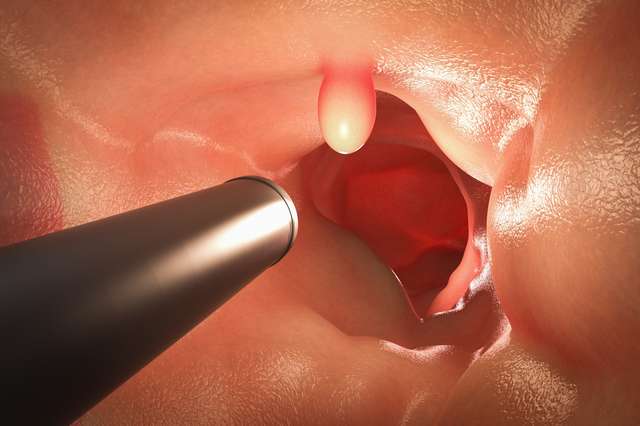

Ein unangenehmer und beängstigender Moment für Patienten mit einer Darmspiegelung. Der Eingriff umfasst die Untersuchung des Rektums, des Dünndarms und...